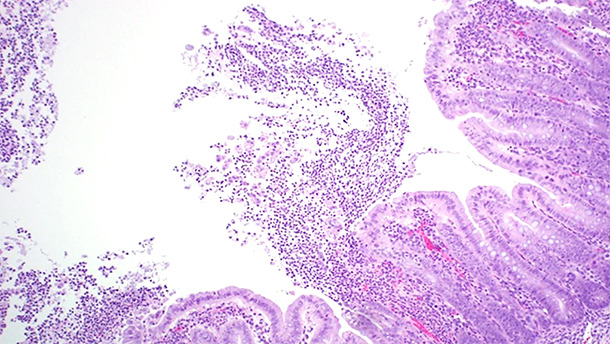

Les lésions associées à l’ICD sont essentiellement concentrées dans le gros intestin. L’œdème du mésocolon (Figure 1) est la lésion macroscopique classique observée dans les cas d’ICD. Toutefois, cette lésion n'est pas pathognomonique; Yaeger et al ont montré que l'œdème du mésocolon chez les porcelets n’est pas un bon prédicteur de toxines de C. difficile (Yaeger et al., 2007). L'examen histopathologique des animaux atteints a révélé une colite ulcérative fibrinopurulente multifocale ou localement étendue (Figure 2).

Figure 2. L’examen histopathologique des animaux atteints a révélé colite ulcérative fibrinopurulente multifocale ou localement étendue.